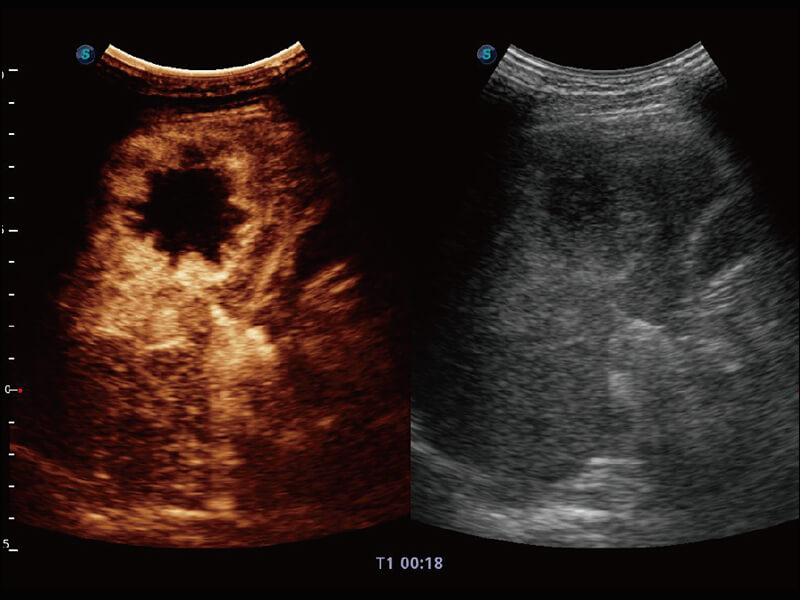

性能优异的硬件架构,极大提升超声系统的运行效率和数据处理能力。相比以往超声成像系统,Wis+平台为您带来极快的响应速度和成像帧频,提升检查流畅度。